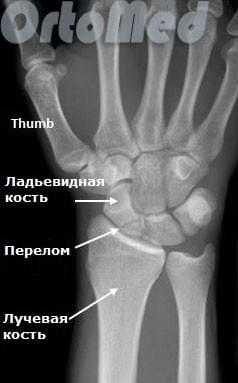

Переломы ладьевидной кости

Любая травма области лучезапястного сустава должна быть оценена врачом травматологом, так как переломы мелких костей могут быть ошибочно расценены пациентом как ушиб. Но последствия перелома ладьевидной кости руки могут быть очень серьезными (см. пояснение в тексте).

Ладьевидная кость является одной из мелких костей запястья. Из всех костей в запястья, переломы ладьевидной кости являются наиболее распространенными. Ладьевидная кость - небольшая кость запястья на стороне большого пальца (с лучевой стороны).

Диагностика переломов ладьевидной кости

Очень важно диагностировать перелом ладьевидной кости как можно раньше, поскольку значительная часть ладьевидной кости имеет плохое кровоснабжение и перелом может не срастись, или наступить некроз фрагмента кости (некровоснабжаемый фрагмент погибает), а это ведет к серьезным отрицательным последствиям (ограничение движений в лучезапястном суставе).

Первым и обязательным диагностическим моментом является рентгенография поврежденного участка конечности. Чаще всего рентгенография ясно показывает характер перелома ладьевидной кости.